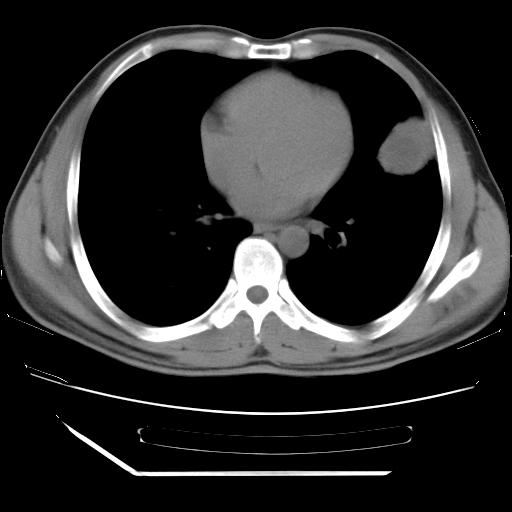

男,38岁,于2009年8月9日晚突发左侧胸痛,今x线提示左下肺阴影,为了明显确诊断,行ct检查,

纵膈窗

病灶发生在下叶,密度均匀,边缘模糊、毛糙,周围血管纹理增强扭曲改变,靠近胸膜处病灶胸膜反应明显。

支持考虑---球形肺炎。

左肺舌叶病变。主体病灶呈类圆形中心密度低,成液化趋势周边班片影分布

考虑肺脓肿

虽然实验室检查支持炎性病变,且病变内有坏死改变(中央呈大片状低密度影),但仍不能掉以轻心,鳞癌也可以有这种影像改变。